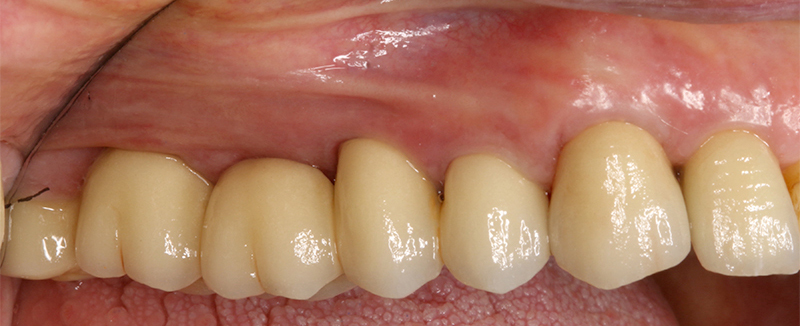

La finalizzazione del caso avveniva con protesi in metallo-ceramica passivata su cappe conometriche in bocca (Figs. 24, 25, 26, 27, 28, 29, 30, 31, 32) e radiografie finali ad un anno dal carico (Figs. 33, 34).

Applicazione ponte 17 - 14 in metallo ceramica su cappette conometriche passivate in bocca mediante cemento Multilink Hybrid e risultato finale

Fig. 25 - Applicazione ponte 17 - 14 in metallo ceramica su cappette conometriche passivate in bocca mediante cemento Multilink Hybrid e risultato finale

Fig. 26 - Applicazione ponte 17 - 14 in metallo ceramica su cappette conometriche passivate in bocca mediante cemento Multilink Hybrid e risultato finale